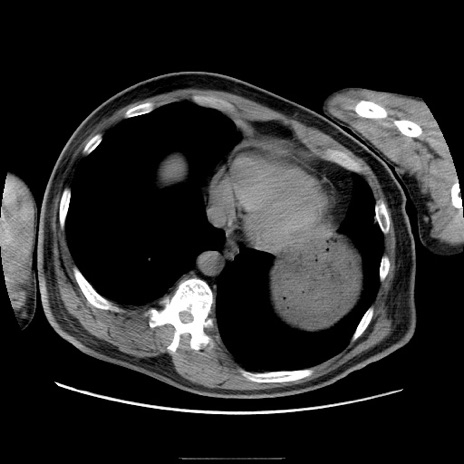

症例22(横断像)

【症例】50歳代男性

【主訴】腹痛

【現病歴】AVMからの被殻出血のため回復期リハ病棟入院中。 本日午後3時頃急に下腹部痛が出現した。

【既往歴】AVM、被殻出血、虫垂炎、高血圧

【身体所見】意識晴明、左半身不全麻痺、会話の理解は良好、36.5°C、腹部:膨隆、全体に板状硬、下腹部正中に圧痛点あり、反跳痛-、筋性防御不明、右下腹部にope scar

【データ】WBC 9400、CRP 0.06